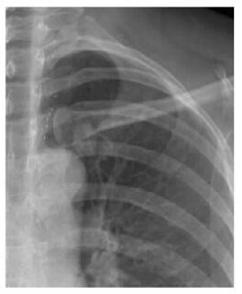

案例二:

圖二 左鎖骨重疊致密結節(jié),誤為衣服紐扣,病理肺腺癌

案例解析:

該病例發(fā)生在國內某基層醫(yī)院,病患首先通過胸片攝影篩查,顯示出左上肺野內帶高密度橢圓形結節(jié),由于形狀與紐扣極為相似,誤為衣服紐扣,并未做進一步診斷。第二年之后,病患再來復查,卻發(fā)現(xiàn)照片上結節(jié)影增大,立即進一步診斷檢查,最終經過活檢證實為肺癌,錯過了最佳的肺癌治療期。